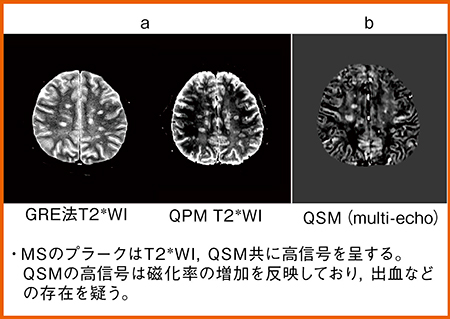

また,磁化率画像(QSM)も作成可能で,GRE法のT2*強調画像と同じように,QPMのT2*強調画像でもプラーク部分に高信号が認められる(図3 a)。また,QSMの高信号は磁化率の増加を反映することから,出血の存在も疑われる(図3 b)。

図3 症例1:QPMによる磁化率画像